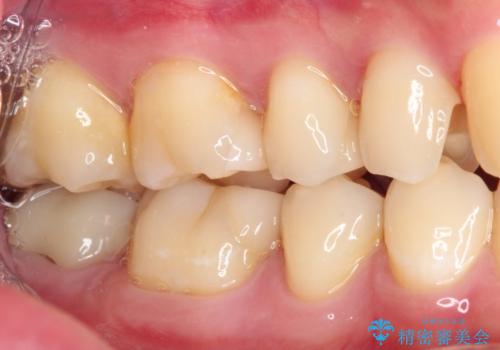

詰め物が外れた セラミックインレー修復

- 以前治療した詰め物が外れてしまい、冷たいものがしみることを主訴として来院された患者様です。

むし歯がないことを確認し、セラミックインレーにて修復するととしました。

適合の良いセラミックインレーの装着により、冷たいものがしみる症状はなくなりました。